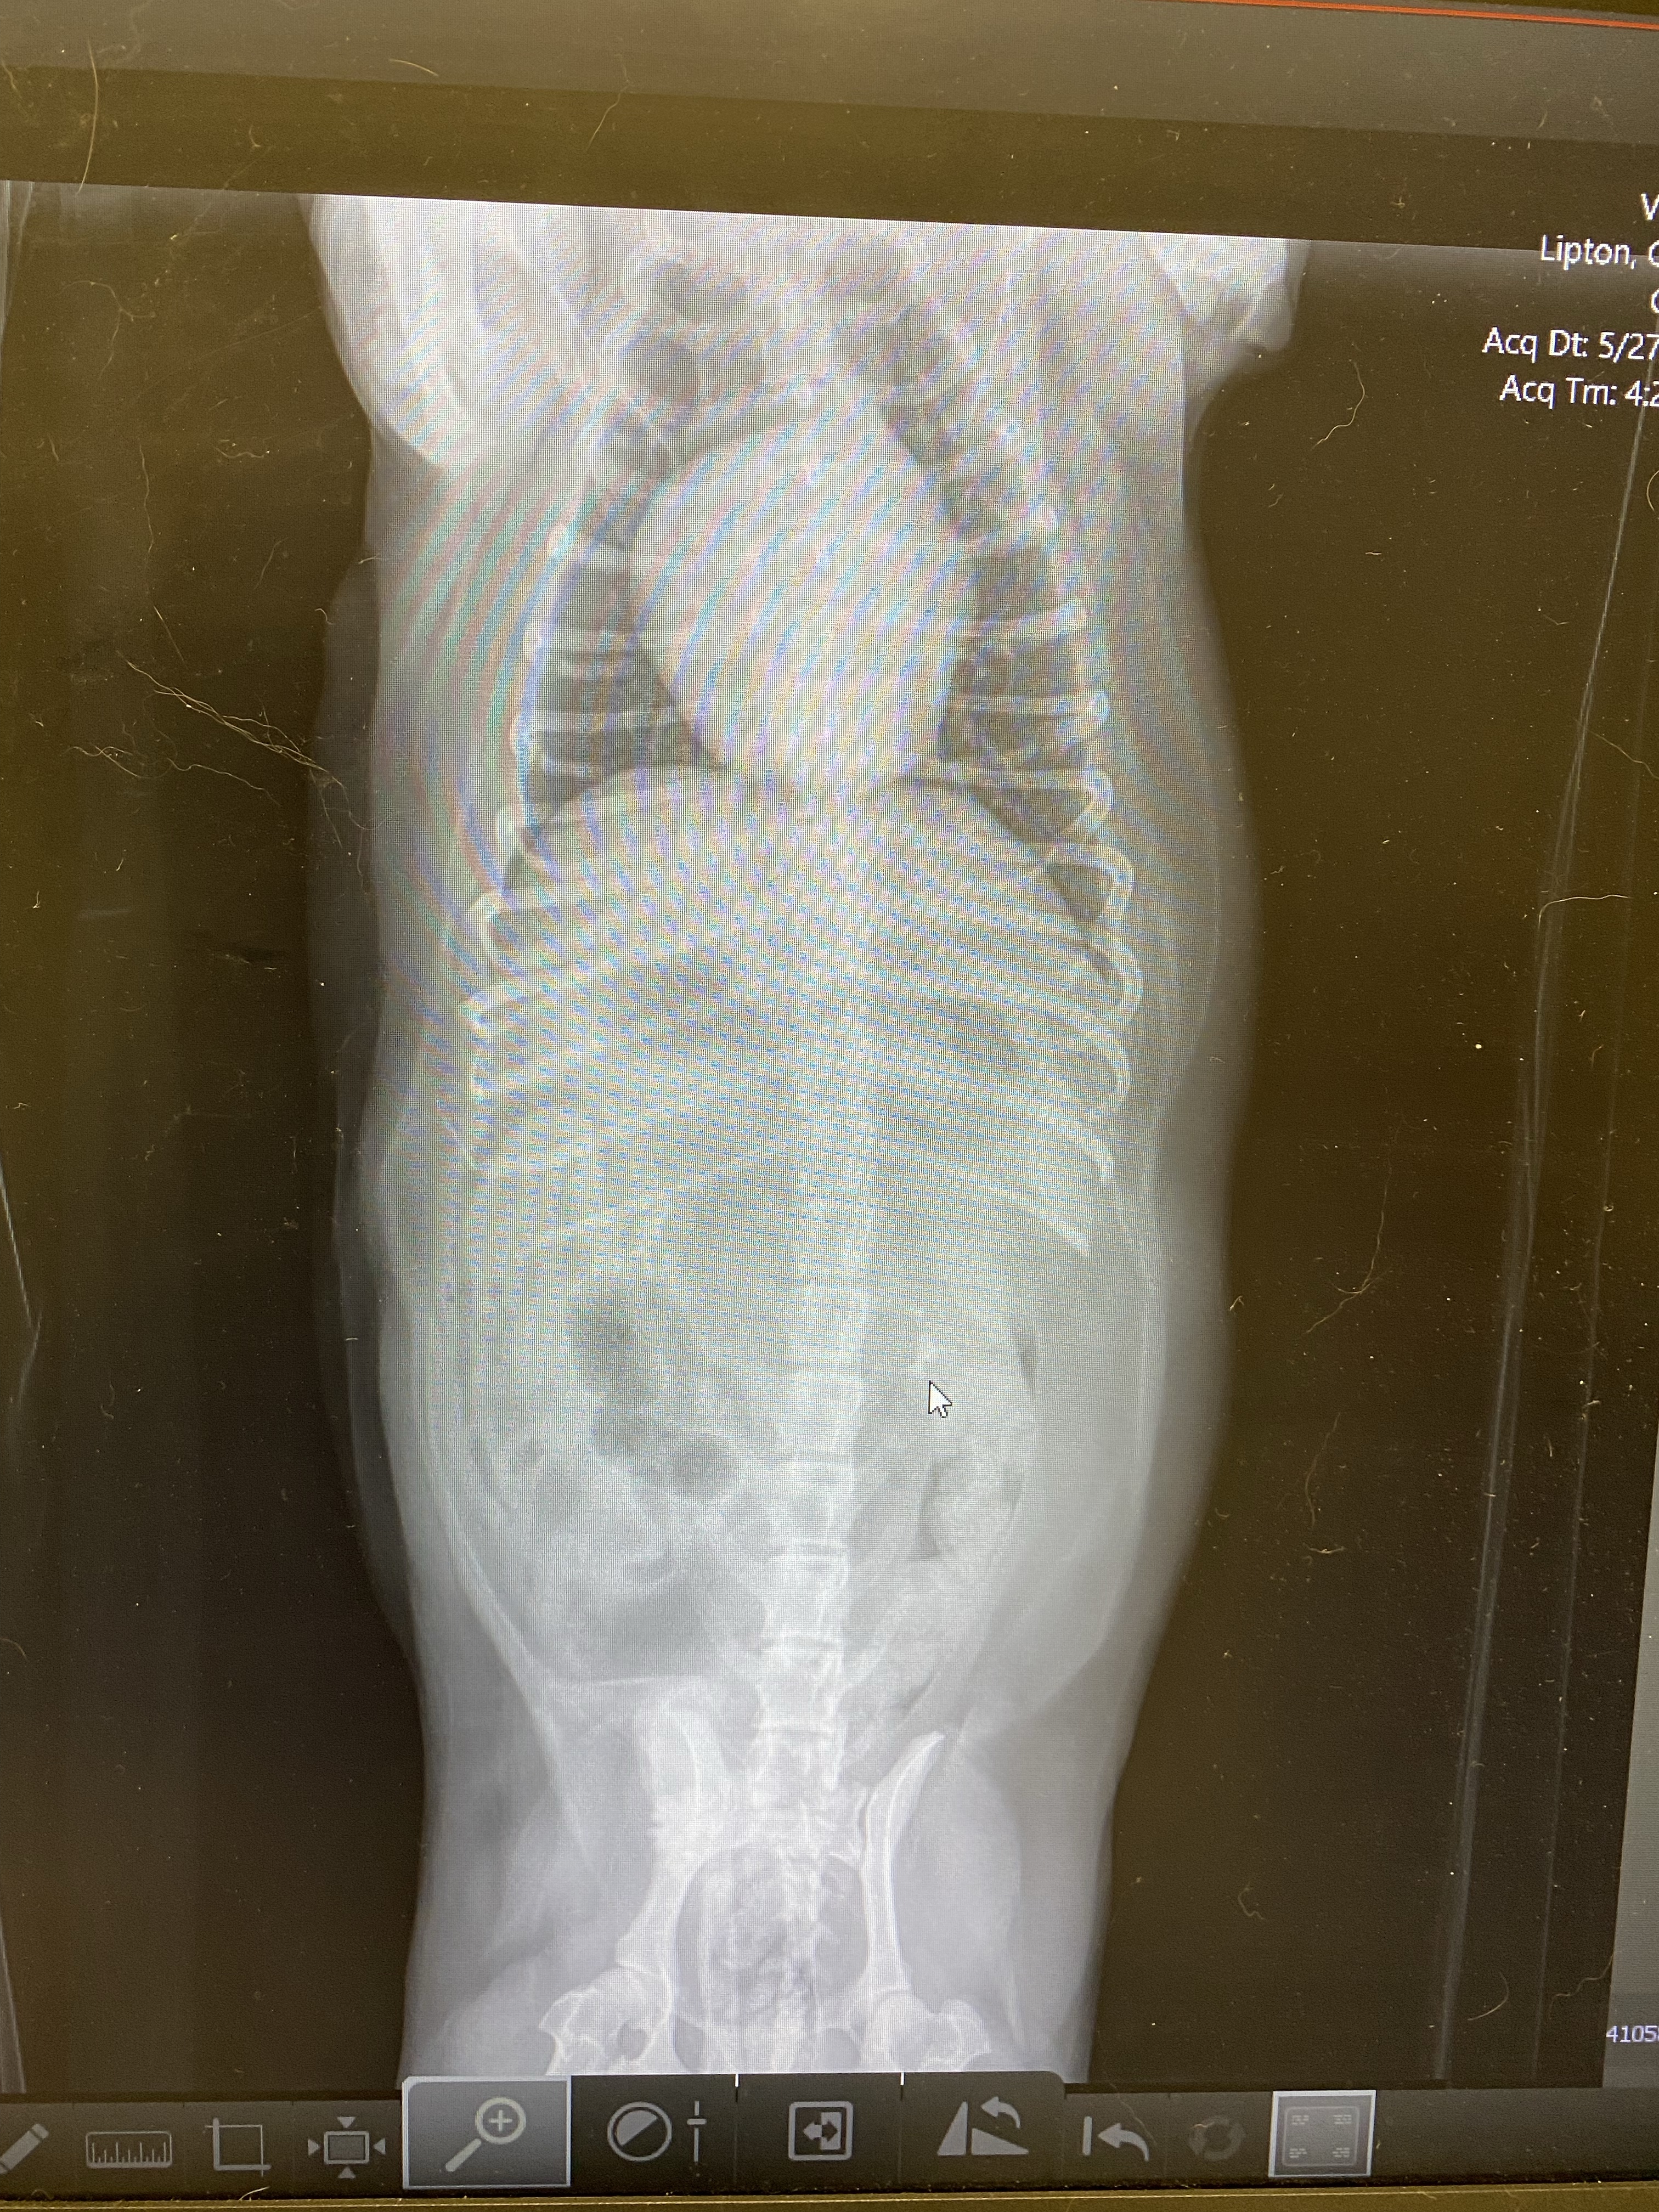

Because Charles has a known heart murmur, she wanted to do an x-ray to see how his heart was doing. Well, we were surprised at what the x-ray told us.

First – Charles’ heart is enlarged. An ENLARGED HEART (dilated cardiomyopathy) is more common in large dogs (our luck). Not knowing the underlying cause we can’t say if it was because of an infection or some structural problem. Right now, we are just in watch mode due to other issues. From the x-ray, his lungs are clear (all that nice dark area around the heart in the ribs is the lungs), which means that they are not currently seeing congestive heart failure (which would be very bad). The vet said that you should be able to fit 3 hearts in that cavity.